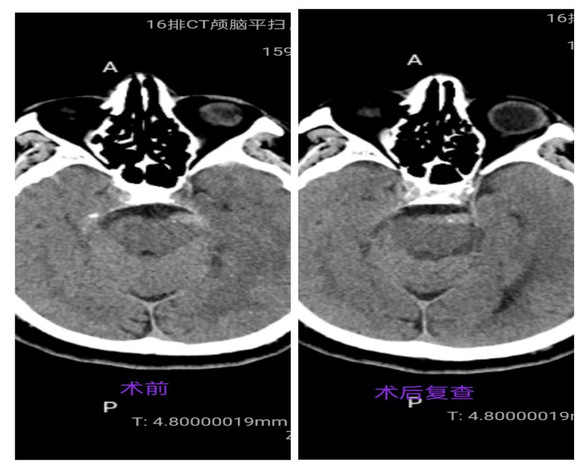

术前术后头部CT平扫

患者术后疼痛消失,成功治愈